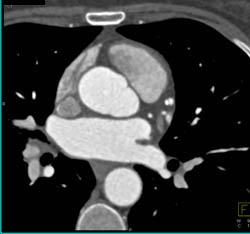

Stenosis in Proximal LAD